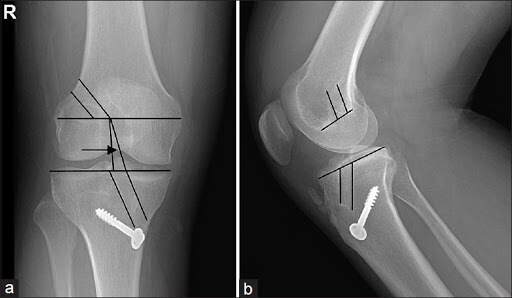

Aceasta metoda ofera imagini mult mai bune ale tesuturilor moi precum ligamentul incrucisat anterior si poate pune diagnosticul de certitudine in ruptura de lia. Ligamentul incrucisat anterior este o banda de tesut conjunctiv de legatura care uneste portiunea posterioara a femurului cu partea anterioara a tibiei de marimea degetului mic. Ligament incrucisat anterior cu edem fibrilar in ansamblu cu elongatii fibrilare ligament incrucisat posterior normal. In interviul acordat echipei sensotv dr.

Ecografia de genunchi este utilă în caz de ruptură a ligamentelor colaterale sau a părții anterioare a meniscurilor însă în cazul rupturii ligamentului încrucișat anterior nu prea ajută. De cele mai multe ori ligamentul se rupe sau se desprinde de la nivelul condilului femural si la rmn este descris ca fiind cazut in posterior. Tratamentul rupturii de ligament incrucisat anterior. Ruptura de ligament încrucișat anterior nu este o leziune foarte gravă.